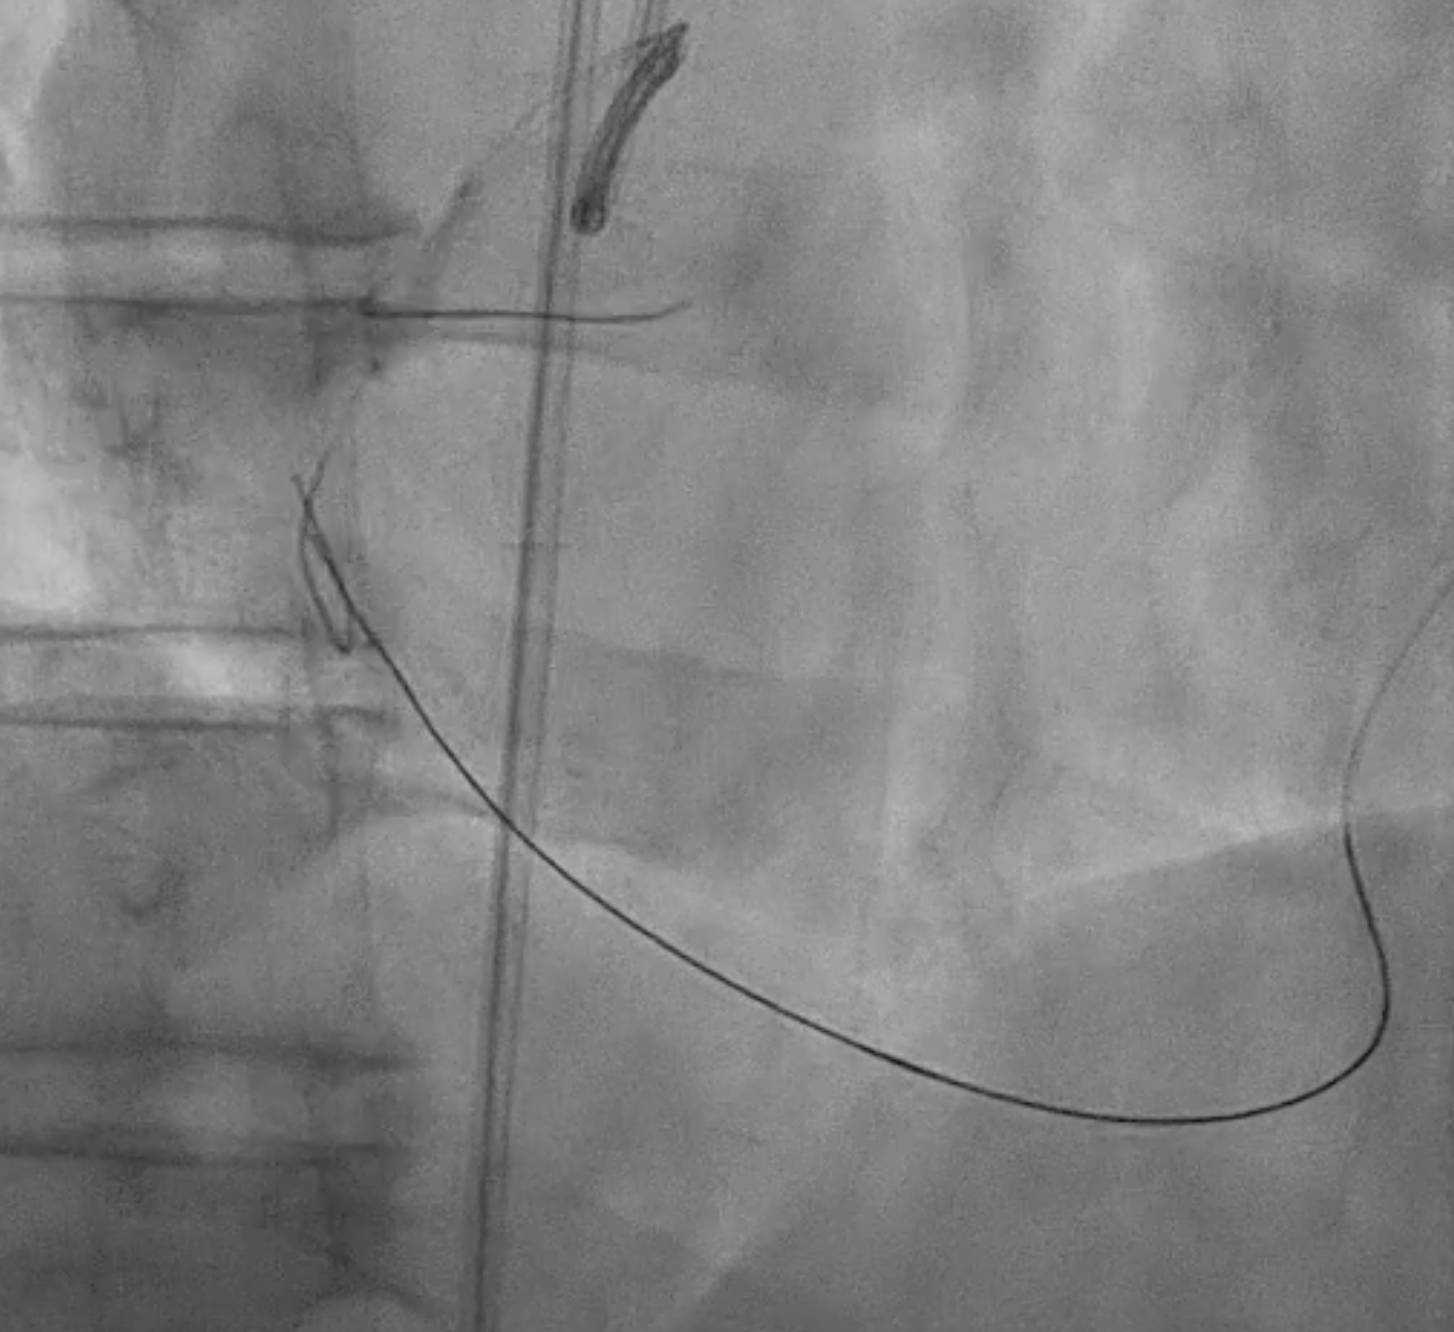

Because the patient presented with acute coronary syndrome, primary PCI was first performed for the culprit lesion, and a drug-eluting stent (DES) was implanted in the proximal LAD. A staged PCI with DES implantation to the proximal LCX was later performed. The initial antegrade attempt for RCA chronic total occlusion (CTO) failed despite wire escalations, as the guidewires could not cross the lesion. Considering the patient¡¯s intolerance and high contrast volume, the procedure was terminated. One month later, the patient was readmitted for complete revascularization. Antegrade wiring with a microcatheter and multiple guidewires (Fielder FC, ULTIMATEbros3, Conquest Pro) again failed to cross the RCA CTO. A retrograde approach using a SION wire via a septal collateral successfully reached the distal RCA. As the retrograde wire could not smoothly re-enter the true lumen, an antegrade wire was used to create a controlled subintimal hematoma, followed by the reverse CART technique. Anchoring balloon support then facilitated microcatheter advancement into the proximal RCA. The rendezvous technique achieved externalization with an ASAHI RG3 330 cm wire, and two Runthrough wires were advanced antegradely into the PDA and PL branches. After sequential balloon dilatation, two DESs (XIENCE Skypoint 2.75 ¡¿ 48 mm and 3.5 ¡¿ 38 mm) were deployed from the distal to the ostial RCA under IVUS guidance. Final angiography showed successful recanalization with TIMI 3 flow.